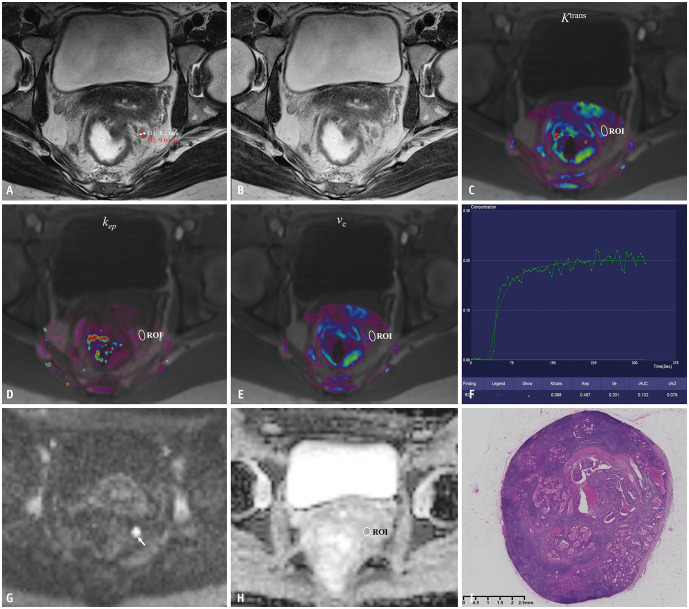

Materials and methods: A retrospective analysis was conducted on 70 patients with rectal cancer, including 168 lesions (70 TDs and 98 MLNs confirmed by histopathology), who underwent pretreatment MRI and subsequent surgery between March 2019 and December 2022. The morphological characteristics of TDs and MLNs, along with quantitative parameters derived from DCE-MRI (Ktrans, kep, and ve) and DWI (ADCmin, ADCmax, and ADCmean), were analyzed and compared between the two groups. Multivariable binary logistic regression and receiver operating characteristic (ROC) curve analyses were performed to assess the diagnostic performance of significant individual quantitative parameters and combined parameters in distinguishing TDs from MLNs.

Results: All morphological features, including size, shape, border, and signal intensity, as well as all DCE-MRI parameters showed significant differences between TDs and MLNs (all P < 0.05). However, ADC values did not demonstrate significant differences (all P > 0.05). Among the single quantitative parameters, ve had the highest diagnostic accuracy, with an area under the ROC curve (AUC) of 0.772 for distinguishing TDs from MLNs. A multivariable logistic regression model incorporating short axis, border, ve, and ADCmean improved diagnostic performance, achieving an AUC of 0.833 (P = 0.027).

Conclusion: The combination of morphological features, DCE-MRI parameters, and ADC values can effectively aid in the preoperative differentiation of TDs from MLNs in rectal cancer.